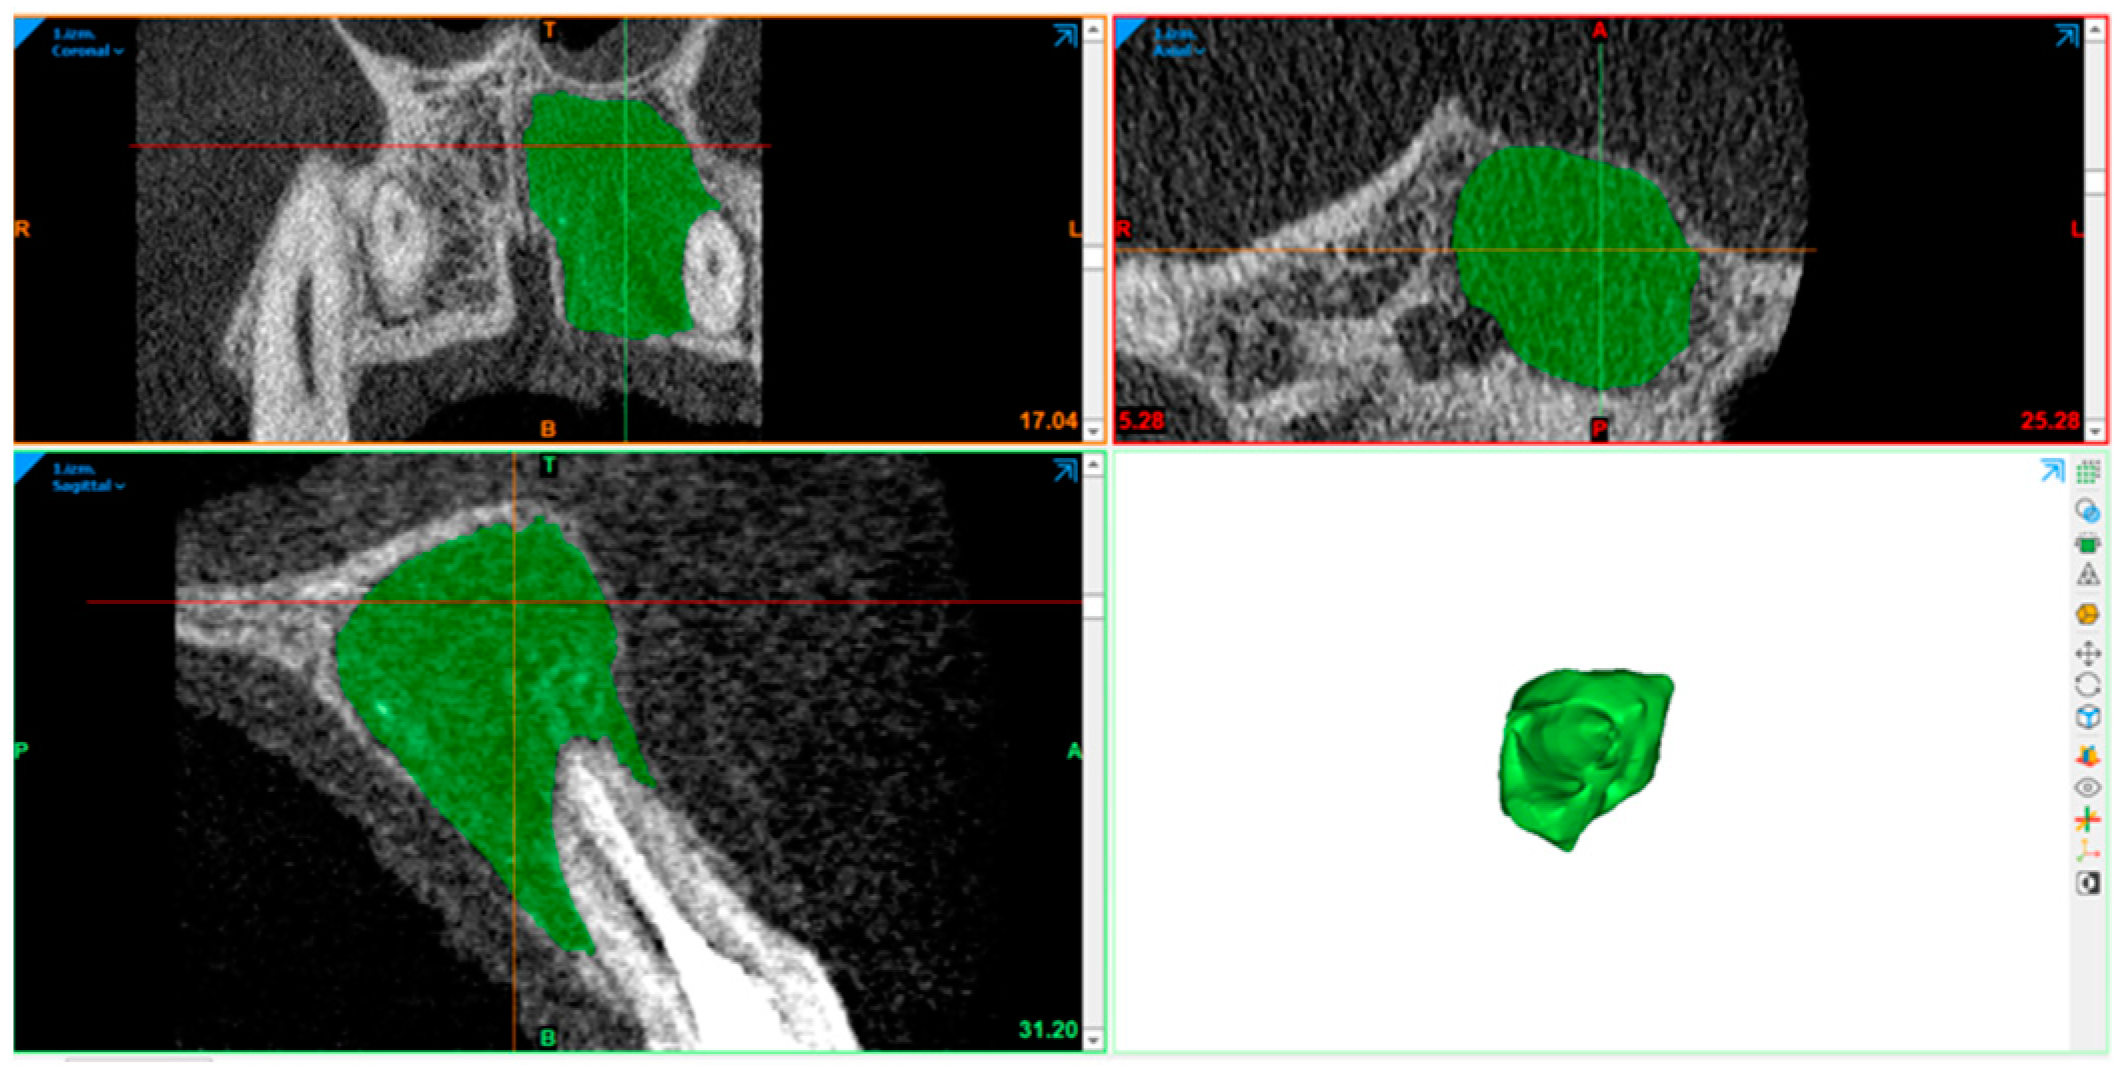

2.10. Radiography Acquisition: Volumetric Assessment

2.11. Statistical Analysis